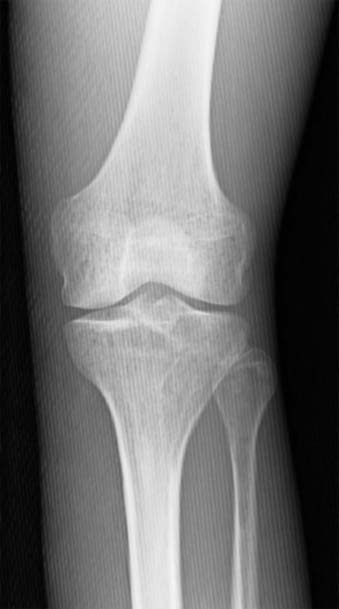

In addition to the disadvantage of increased patient dose associated with grid use, another disadvantage is the possibility of grid cutoff. Grid cutoff refers to a decrease in the number of transmitted photons that reach the IR because of some misalignment of the grid. The primary radiographic effect of grid cutoff is a further reduction in the number of photons reaching the IR. Grid cutoff may require the radiographer to repeat the radiographic image, increasing patient dose yet again. Grid ratio has a significant impact on grid cutoff, with higher grid ratios resulting in more potential cutoff.

Grid cutoff can occur because of four types of errors in grid use. To reduce or eliminate grid cutoff, the radiographer must have a thorough understanding of the importance of proper grid alignment in relation to the IR and x-ray tube.

Upside-down focused grid cutoff occurs when a focused grid is placed upsidedown on the IR, resulting in the grid lines going opposite the angle of divergence of the x-ray beam resulting in a significant loss of exposure along the edges of the image (Fig. 7-22). Photons easily pass through the center of the grid because the lead lines are perpendicular to the IR surface. Lead lines that are more peripheral to the center have steeper angles and absorb the transmitted photons. Upside-down focused grid error is easily avoided because every focused grid should have a label indicating the tube side. This side of the grid should always face the tube, away from the IR.

FIG. 7-22 Radiographic image produced with an upside-down focused grid.

Off-level grid cutoff results when the x-ray beam is angled across the lead strips. It is the most common type of cutoff and can occur from either the tube or the grid being angled (Fig. 7-23). Off-level grid cutoff can often occur with mobile radiographic studies or horizontal beam examinations and is visualized as a loss of exposure across the entire IR. This type of grid cutoff is the only type that occurs with both focused and parallel grids.

FIG. 7-23 An off-level grid can cause grid cutoff.

Also called lateral decentering, off-center grid cutoff occurs when the central ray of the x-ray beam is not aligned from side to side with the center of a focused grid. Because of the arrangement of the lead lines of the focused grid, the divergence of the primary beam does not match the angle of these lead strips when not centered (Fig. 7-24). Off-center grid cutoff may cause an overall loss of exposure across the entire IR.

FIG. 7-24 Centering to one side of a focused grid can cause off-center grid cutoff.

Off-focus grid cutoff occurs when using an SID outside the recommended focal range. Grid cutoff occurs if the SID is less than or greater than the focal range and results in a loss of exposure at the periphery of the IR.